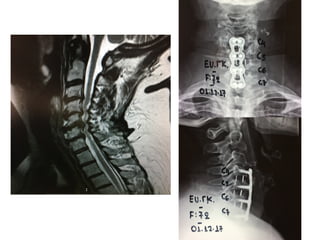

Cervical stenosis - Myelopathy

Anterior decompression and stabilization

with Mesh cylinder and plate

Cervical arthritis and stenosis

Corpectomies and Anterior stabilization